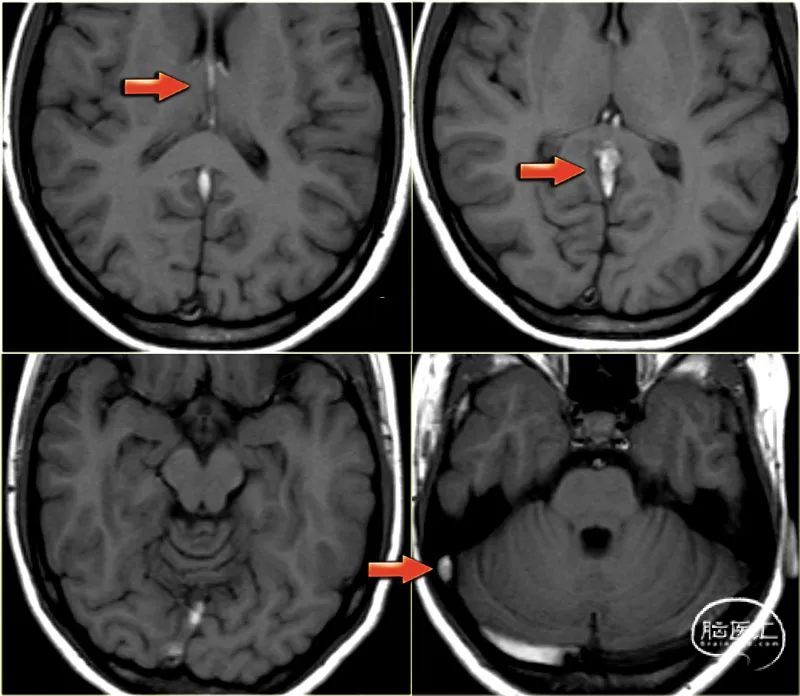

下图左显示左侧丘脑的高信号。

当你仔细观察时,右侧基底节区也有高信号。

这些双侧发现应引起对脑深静脉血栓形成的怀疑。

矢状位CT重建显示直窦和Galen静脉(箭头)有充盈缺损。

下图是双侧基底节区异常的年轻患者。

根据影像学表现,有一个广泛的区别,包括小血管疾病,脱髓鞘,中毒和代谢紊乱。

注意大脑内静脉和直窦的异常高信号在T1加权图像上。

诊断为深静脉血栓所致基底节双侧梗死。